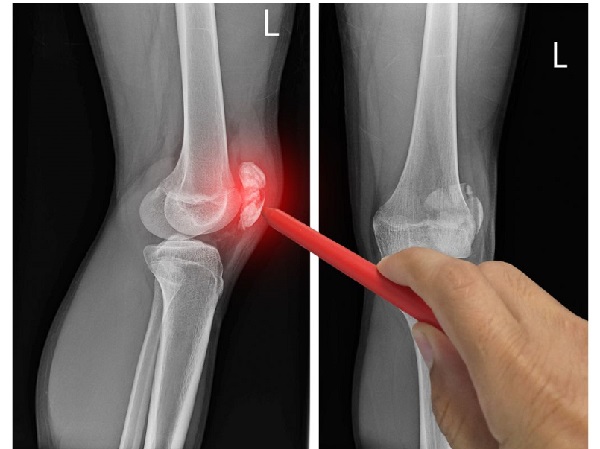

3. Inflamación crónica

No solo la mecánica daña las articulaciones, sino también la bioquímica.

Los procesos inflamatorios asociados con la diabetes, la gota e incluso el estrés crónico dañan el cartílago.

Según el Journal of Rheumatology (2019), las personas con síndrome metabólico desarrollan osteoartritis dos veces más rápido, incluso sin obesidad.